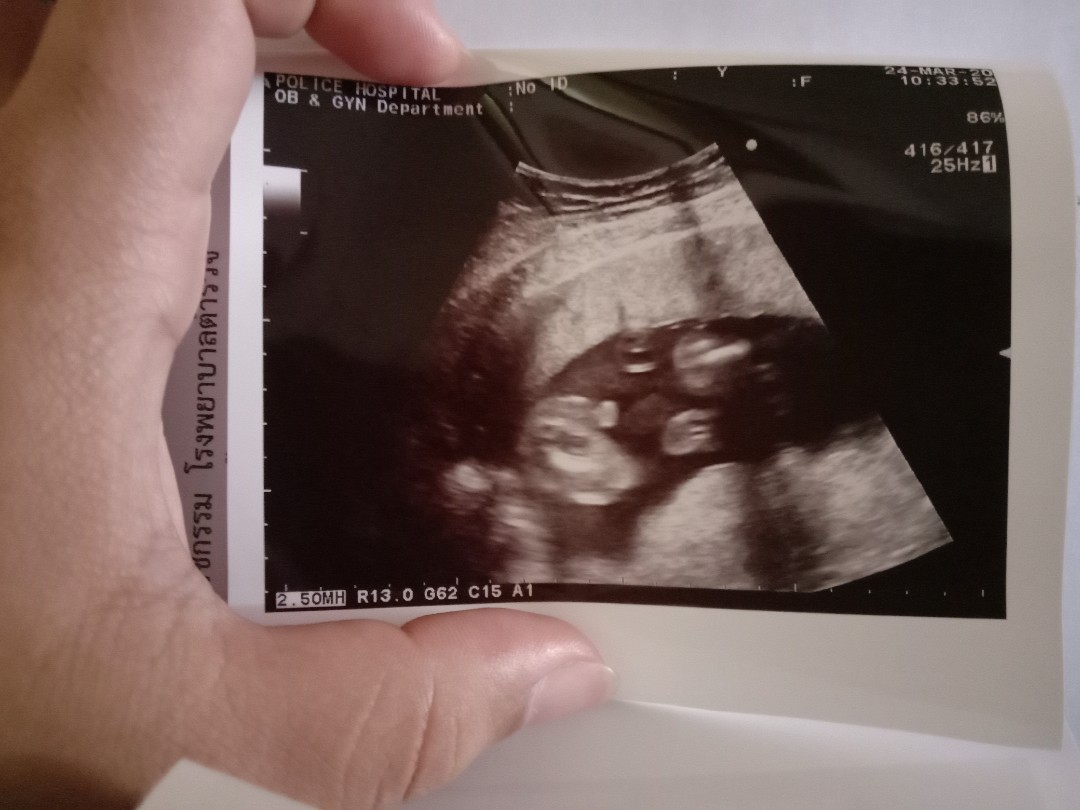

ใบซาวด์

ขอดูใบซาวด์เเม่ๆคลอดเดือนก.คหน่อยค่ะได้ผญหรือผชกันค่ะ